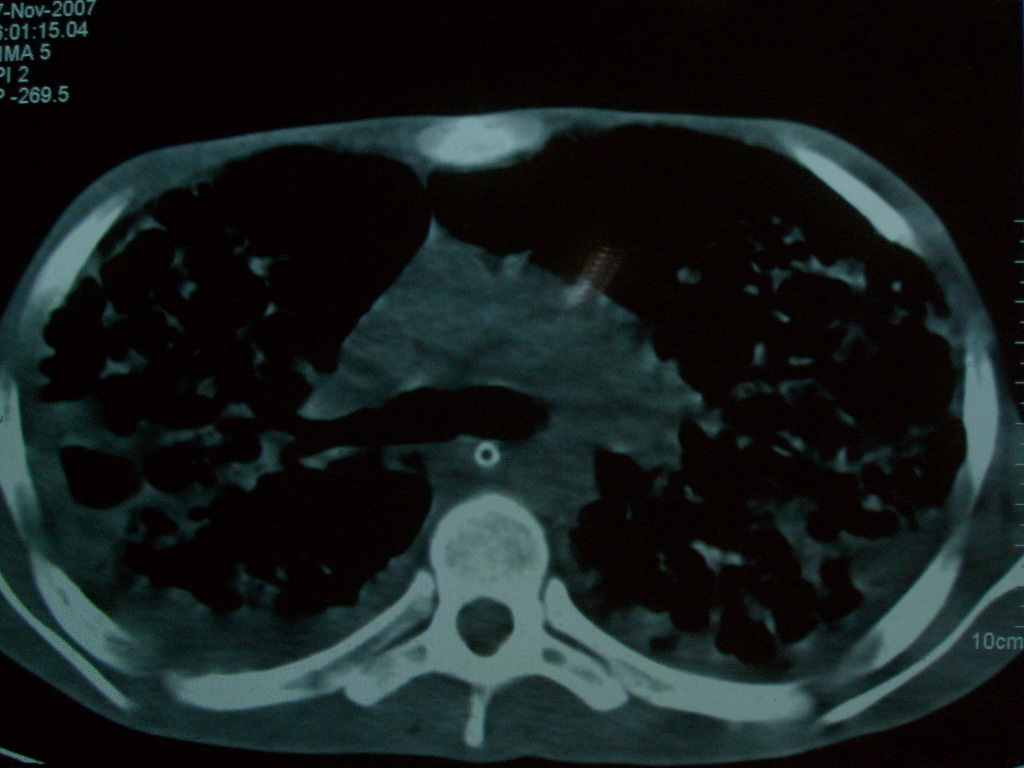

标题: CT10510:男.18岁,咳嗽咳痰两月.(有病理) [打印本页]

标题: CT10510:男.18岁,咳嗽咳痰两月.(有病理)

双肺布满大片状实变及网格状结节影,内参杂大小不等的气囊及空气支气管征,心脏增大。考虑:1 全身结缔组织疾病—系统性红斑狼仓?2 肺泡蛋白沉积症合并感染!

双肺布满大片状实变及网格状结节影,内参杂大小不等的气囊及空气支气管征,双侧胸膜腔少量积液,双下肺近膈面透亮度尚可,病人较年轻,病变较重(不知为什么上胃管?)考虑:1.胶原病肺部改变,2.组织细胞病x。结合实验室检查。

首先考虑组织细胞x病。两肺中上肺野多发囊腔,中下肺野内见多发小结节,并可见肺间质增厚。患者是男性,年龄较小。胶原性病变比较多见的类风湿、系统性红斑狼疮和硬皮病临床和影像均不是很支持,类风湿和系统性红斑狼疮的肺部表现最常见的是胸腔积液,硬皮病可见食管的扩张。

肺内多发斑片状、结节状、融合大片状及网格状影,多发薄壁空腔影,胸膜肥厚,纵隔、气管右移,考虑ⅲ型肺结核,多发空洞,继发肺间质纤维化。

双肺结核并播散.患者以肠梗阻入院,手术为肠结核.术后咳嗽做ct检查.